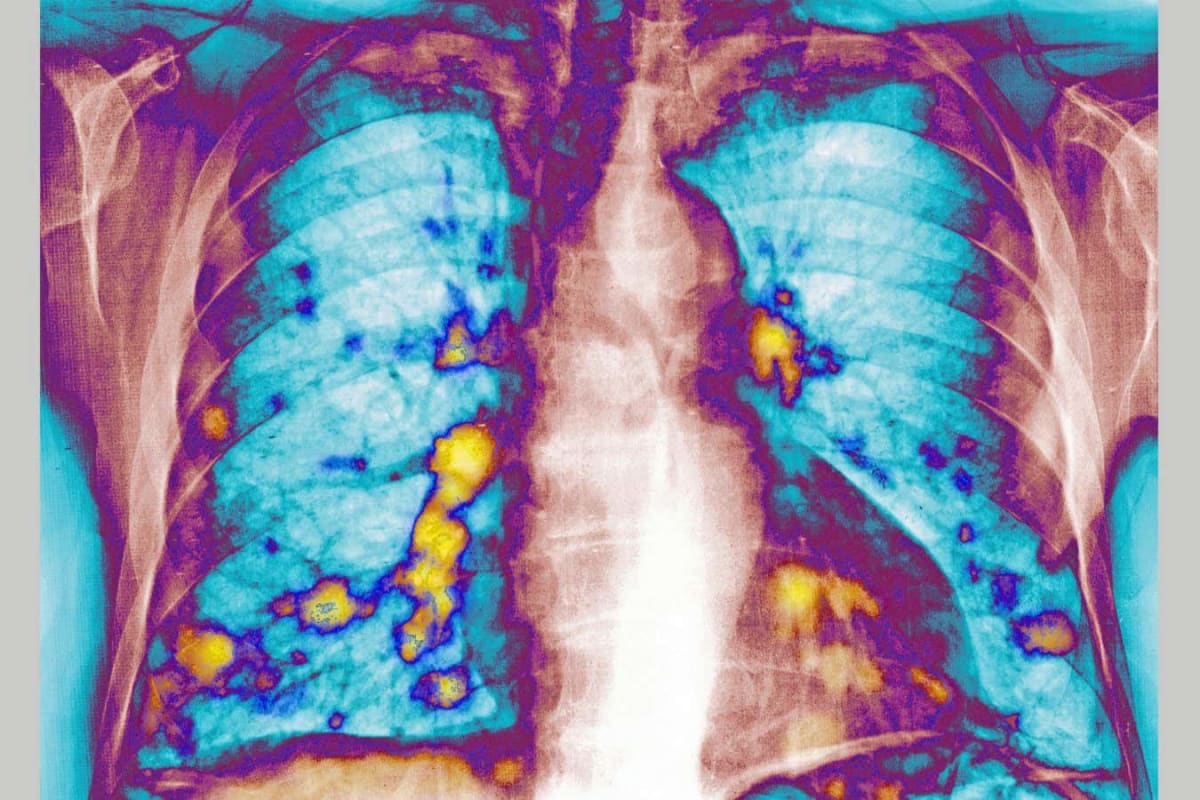

Scientists at the University of Colorado have discovered how to eliminate cancer cells that survive initial treatment, potentially turning lung cancer into a curable disease. The breakthrough combines two therapies to attack cancer at its most vulnerable moment.

The problem has frustrated doctors for years. Current drugs called tyrosine kinase inhibitors can destroy 98% to 99% of lung cancers driven by the HER2 gene mutation. But a small number of cells always survive by adapting and hiding from the treatment.